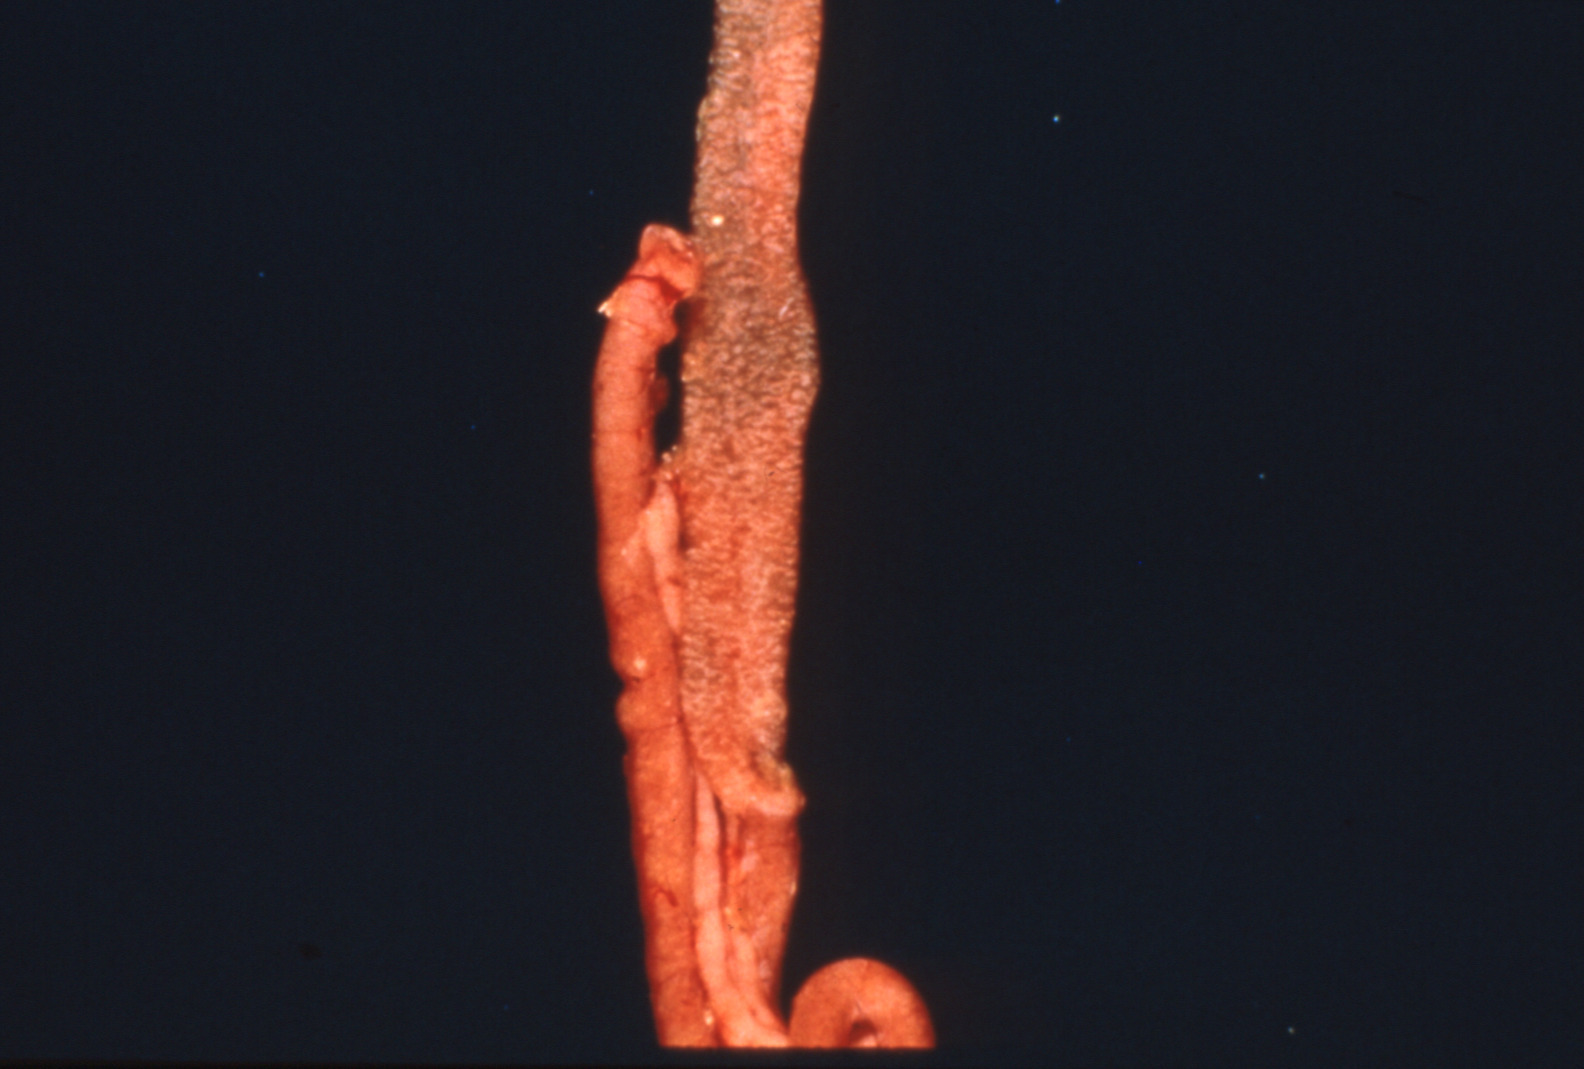

Coccidiosis in chickens and turkeys (slide study set no. 7)

Avian coccidiosis Avian medicine Chickens--Diseases Turkeys--Diseases